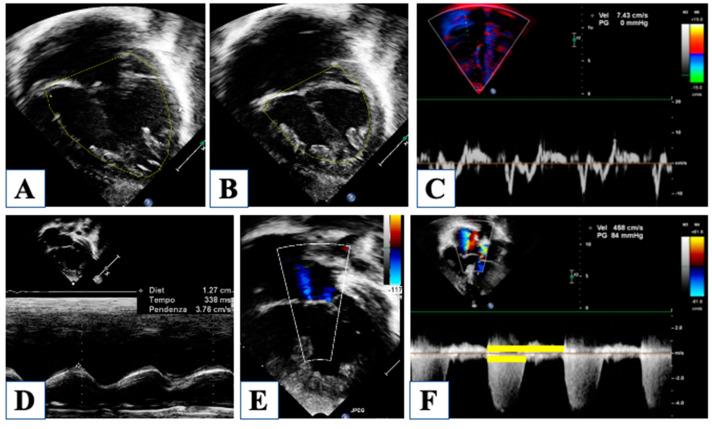

Hypoplastic left heart syndrome is a spectrum of complex congenital cardiac defects. Although in borderline cases, biventricular repair is a viable option, in the majority of cases, univentricular palliation is the treatment of choice. Hybrid palliation can be a valid alternative to classic Norwood operation in the neonatal period, especially in selected cases such as high-risk patients or borderline left ventricles. Echocardiography is the main diagnostic modality in this pediatric population, from the fetal diagnosis to the subsequent surgical steps of palliative treatment. Hybrid palliation is performed after birth and is characterized by surgical banding of the pulmonary arteries along with transcatheter stenting of the ductus arteriosus. There are some peculiar aspects of cardiac imaging that characterize this type of palliation, and that should be considered in the different phases before and after the procedure. We aimed to review the current literature about the role of echocardiography in the management of patients with hypoplastic left heart undergoing hybrid palliation.

左心发育不全综合征是一系列复杂的先天性心脏缺陷。虽然在临界病例中,双心室修复是一种可行的选择,但在大多数情况下,单心室姑息治疗是首选的治疗方法。在新生儿期,杂交姑息治疗可以是经典诺伍德手术的有效替代方案,特别是在某些特定病例中,如高危患者或临界左心室。从胎儿诊断到后续姑息治疗的手术步骤,超声心动图是这一儿科人群的主要诊断方式。杂交姑息治疗在出生后进行,其特点是对肺动脉进行外科束带术并对动脉导管进行经导管支架置入术。心脏成像有一些特殊方面是这种姑息治疗的特征,并且在手术前后的不同阶段都应予以考虑。我们旨在综述当前关于超声心动图在接受杂交姑息治疗的左心发育不全患者管理中的作用的文献。